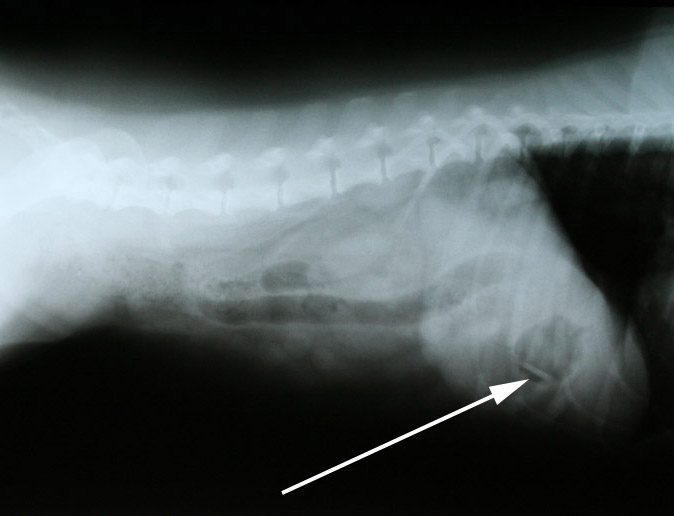

en op de andere foto’s wel: